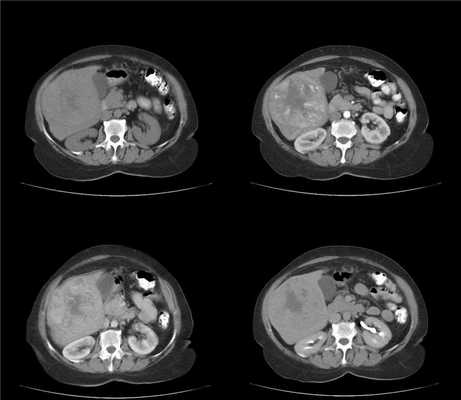

(Слева) На аксиальной КТ с контрастным усилением определяется вертикально ориентированный гиподенсный участок, распространяющийся от краниальных до каудальных отделов печени, отграниченный прямой демаркационной линией, обусловленный лучевой терапией по поводу лимфомы.

(Справа) На аксиальной КТ с контрастным усилением визуализируется ровная демаркационная линия, отделяющая поврежденный участок в левой доле печени, обусловленный лучевой терапией по поводу рака пищевода. Обратите внимание, что левая печеночная вена, проходящая в поврежденном участке печени, не выглядит патологически измененной. (Слева) На аксиальной КТ определяется снижение плотности задних сегментов печени, отделенных от не измененной паренхимы четкой демаркационной линией. Гиподенсные участки паренхимы соотносятся с зоной, подвергнутой эмболизации с использованием микросфер иттрия-90, по поводу гепатоцеллюлярного рака. Обратите внимание, что задняя ветвь правой долевой ветви воротной вены, проходящая внутри измененного участка паренхимы печени, выглядит обычно.

(Справа) На КТ с контрастным усилением у этого же пациента визуализируются жизнеспособные сателлитные очаги ГЦР в передних сегментах печени, которые не подвергались облучению.

(Слева) На КТ в артериальной фазе контрастного усиления у мужчины 66 лет с известным гепатоцеллюлярным раком (до начала терапии) визуализируется неравномерно гиперваскулярное образование в печени.

(Справа) На КТ в портально-венозной фазе у этого же пациента не определяется каких-либо патологических изменений со стороны паренхимы печени. (Слева) На КТ без контрастного усиления, выполненной повторно во время лечения (внутриартериального введения микросфер иттрия-90), определяется гиподенсный участок клиновидной формы, расположенный в зоне кровоснабжения правой долевой ветви печеночной артерии, и соответствующий распределению радиоактивных микросфер.

(Справа) На КТ в артериальной фазе у этого же пациента сохраняется клиновидный участок лучевого повреждения печени. Обратите внимание на ровную демаркационную линию, ограничивающую повреждение. (Слева) На КТ в венозной фазе контрастного усиления у этого же пациента определяется снижение васкуляризации узла ГЦР по сравнению с КТ-исследованием, выполненным до лечения. Обратите внимание на сохраняющуюся ровную демаркационную линию, отграничивающую сегменты печени, подвергнутые облучению.

(Справа) На заключительной КТ в венозной фазе контрастного усиления у этого же пациента визуализируются интактные кровеносные сосуды, проходящие внутри зоны радиационно-индуцированного поражения печени. Какой-либо клинической симптоматики у пациента не обнаруживается, имеет место лишь легкое повышение уровня печеночных трансаминаз.

(Справа) На КТ в артериальной фазе у этого же пациента сохраняется клиновидный участок лучевого повреждения печени. Обратите внимание на ровную демаркационную линию, ограничивающую повреждение. (Слева) На КТ в венозной фазе контрастного усиления у этого же пациента определяется снижение васкуляризации узла ГЦР по сравнению с КТ -исследованием, выполненным до лечения. Обра -тите внимание на сохраняющуюся ровную демаркационную линию, отграничивающую сегменты печени, подвергнутые облучению.

(Слева) На аксиальной КТ с контрастным усилением у мужчины 65 лет, которому проводилась лучевая терапия по поводу рака пищевода с метастазами в левую долю печени, визуализируются гипо- и гиперденсные очаги в левой и хвостатой долях печени, отграниченные от неизмененной паренхимы печени четкой демаркационной линией, определяющей границы области облучения.

(Справа) На КТ в венозной фазе контрастного усиления у этого же пациента визуализируются очаги различной плотности в зоне облучения, не соответствующей анатомическому сегментарному делению печени, обусловленные радиационным гепатитом. (Слева) На аксиальной КТ с контрастным усилением у женщины 26 лет с известным раком носоглотки и метастазами в печень визуализируется гиподенсная «полоска» в центральных отделах печени. Обратите внимание на отсутствие объемного воздействия на крупные ветви воротной и печеночной вен, расположенных внутри измененного участка печени.

(Справа) На этом же КТ срезе в «костном» электронном окне определяется один из нескольких метастазов в позвоночник, по поводу которых также осуществлялась дистанционная лучевая терапия. (Слева) На корональной КТ у этой же пациентки визуализируется гиподенсная «полоска» в печени, соотносящаяся с радиационно-индуцированным поражением ее паренхимы. Обратите внимание на отсутствие объемного воздействия на кровеносные сосуды в пораженном участке, а также на метастазы в печени.

(Справа) На аксиальной КТ с контрастным усилением, выполненной спустя четыре месяца этой же пациентке, определяется регресс изменений, обусловленных облучением, наряду с уменьшением размеров одного из метастазов в печени, что, скорее всего, является эффектом химиотерапии, а не лучевого воздействия.